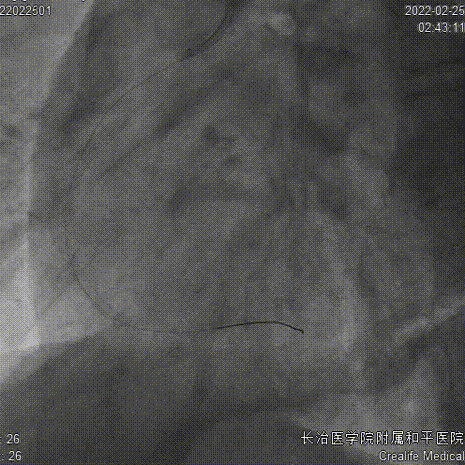

CAG

复查CAG